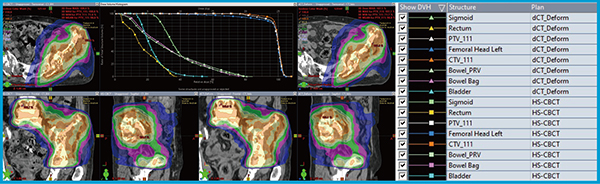

経過観察目的にて撮影されたdCT画像を用いて線量分布を比較した。PTVの最大線量の差は0.7%,総MUの誤差は0.2%(1.1MU)であり,線量体積ヒストグラム(DVH)は良好に一致した(図4)。

図4 症例1におけるHS-CBCT(左)とdCT(右)の線量分布の比較